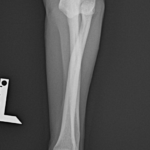

2歳の柴犬ちゃんが、生まれてすぐに痛めた肘に徐々に痛みが出てきたとのことで、主治医から診察と必要があれば手術をして欲しいと連絡がありました。CTでは橈骨頭が外側に脱臼して変位していました。また回転性の変形を伴っています。同時に尺骨にも湾曲が認められています。このような変形矯正には3Dプリンターで模擬手術を行いあらかじめシミュレーション手術をしておくと時間の短縮と正確な変形矯正が可能となります。このようなテクノロジーを動物医療にもどんどん取り入れていきたいと思います。また、骨きり部位にはPRFと自家海綿骨移植を行い治癒促進を期待します。